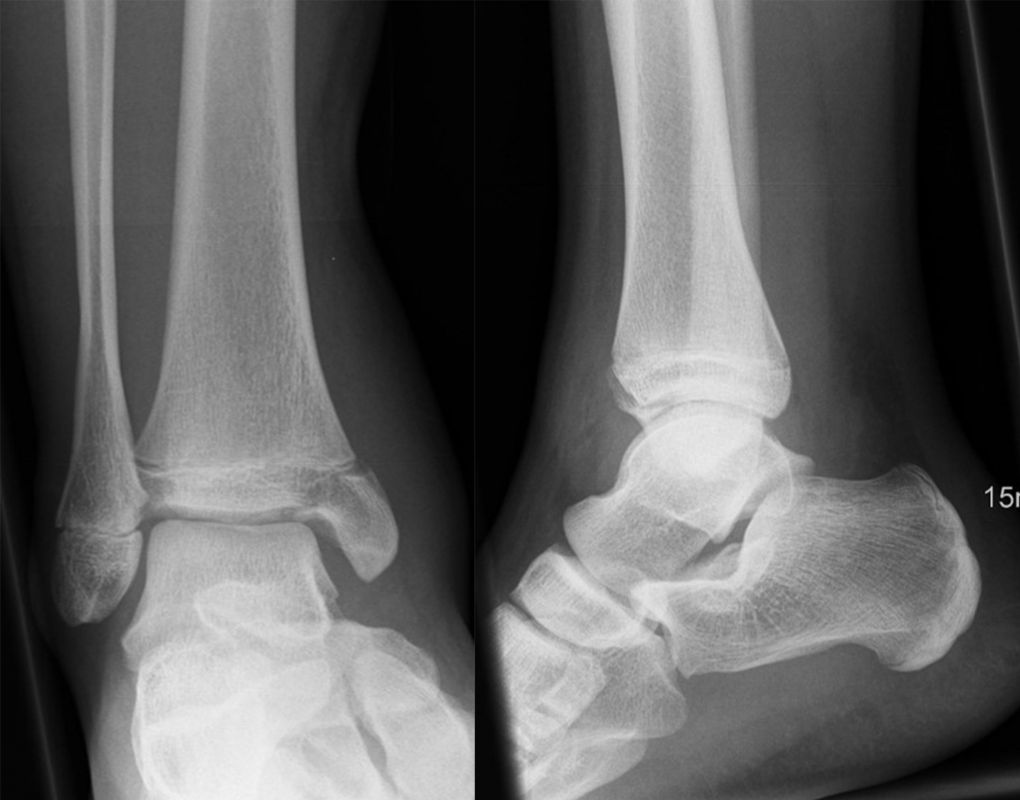

Röntgen

Die Standard Röntgendiagnostik des Sprunggelenks umfasst Bilder in anteriorposterioren (a.p.) und im seitlichen Strahlengang 6. Für die exakte Abbildung des Innenknöchels müssen beide Malleolen parallel zur Röntgenplatte zu liegen kommen. Je nach Torsion der Tibia macht dies eine Innenrotation des Fußes zwischen 10° und 30° erforderlich (Abb. 3).

Manchmal sind mediale Malleolarfrakturen nur in einer der Aufnahmen in ihrem Ausmaß erkennbar. Keine Rolle spielt die gehaltene Aufnahme beim Kind, insbesondere bei der akuten Verletzung. In seltenen Fällen hat dieses Verfahren bei Verdacht auf eine chronische Instabilität eine Berechtigung.